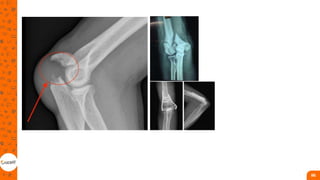

COTOVELO

• Cabeça do radio: São as

fraturas mais comuns do

cotovelo, com maior incidência

em homens jovens (traumas de

alta energia) e mulheres mais

velhas com quedas

(DUCKWORTH et al., 2012).

COTOVELO • Cabeça doradio: São as fraturas mais comuns do cotovelo, com maior incidência em homens jovens (traumas de alta energia) e mulheres mais velhas com quedas (DUCKWORTH et al., 2012). Existe um alto índice de lesões ligamentares e osteocartilaginosas associadas, geralmente necessitando de exames complementares. • quedas da própria altura ou trauma de alta energia em adultos jovens. A força direta na ponta do cotovelo resulta em um fragmento deslocado, o qual migra proximalmente, devido à tração da inserção do tríceps em pacientes jovens. Em idosos, pode haver fratura por avulsão do olecrano ao tentarem evitar uma queda mantendo a contração vigorosa do tríceps 85